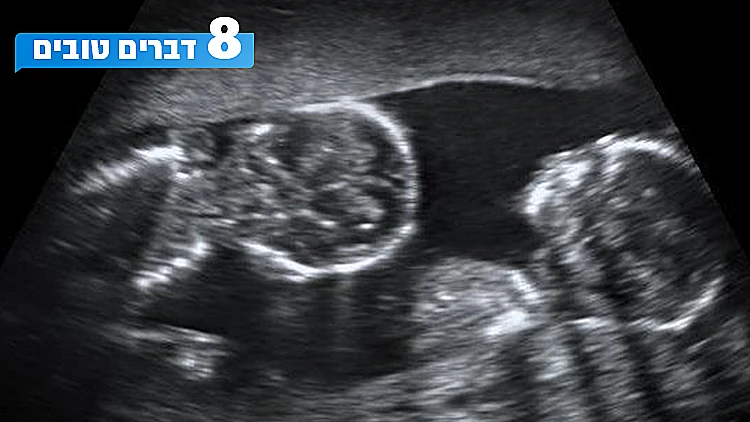

ילדה תאומים לא זהים - וגילתה כי לכל תינוק אב אחר

חשבתם שהמשפחה שלכם מוזרה? חכו שתשמעו על האישה האמריקנית שגילתה לתדהמתה שהתאומים שלה הם לא מאותו אבא. מסתבר שזה קורה באחת מתוך מיליון לידות תאומים. איך בדיוק זה קורה ואיך הגיב בן הזוג שגילה שרק אחד מהילדים שלו?